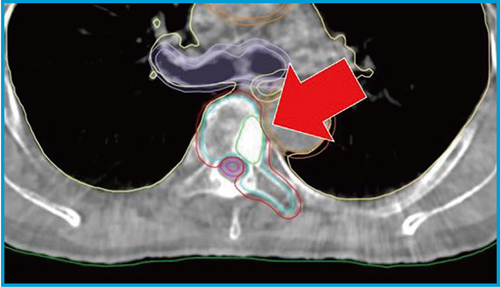

図2に,実際の HyperSight CBCTを示す。←で示したGTV(緑色のライン)が鮮明に視認可能であることがわかる。

図2 椎体定位照射におけるHyperSight CBCT画像

(ストラクチャー含む,GTV=緑色のライン)